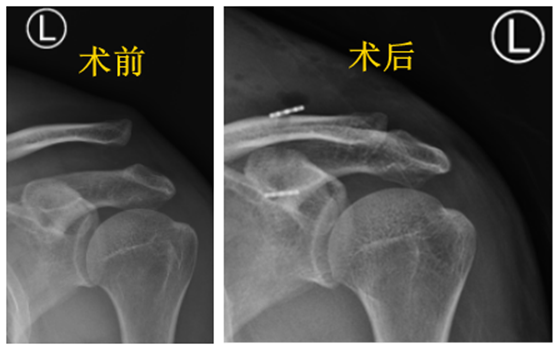

9月21日,49岁的王先生因跌倒造成左肩关节活动受限,为求治疗来到湘雅常德医院关节骨科就诊,经副主任医师史瑞超详细检查后发现,患者左肩关节疼痛明显,肩关节活动困难,左肩锁骨较左...